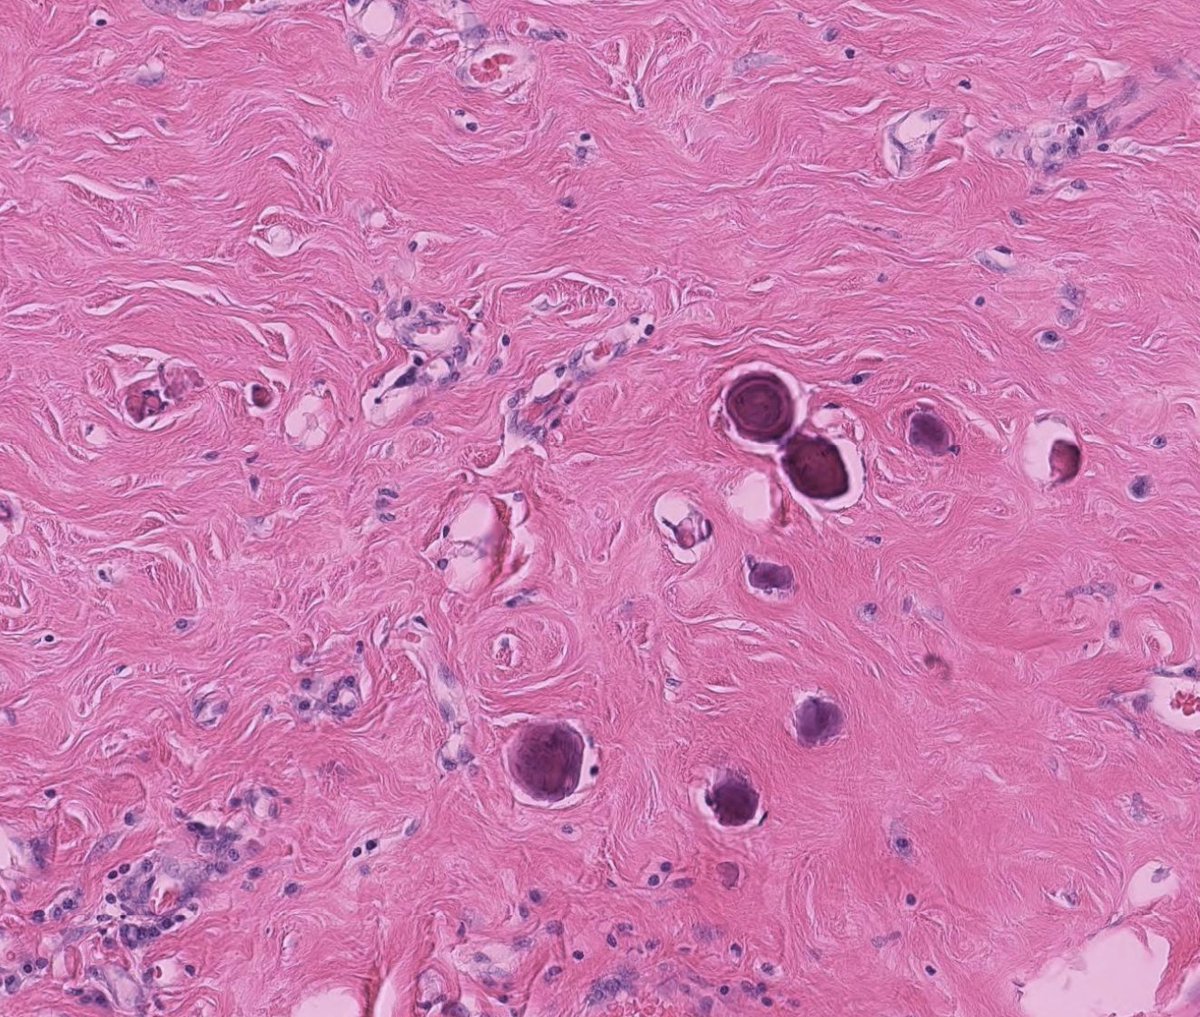

Couldn't be more excited to announce the launch of pathlibrary.com, the virtual slide site I wish had existed during my pathology residency. You can:

- See annotated histologic features